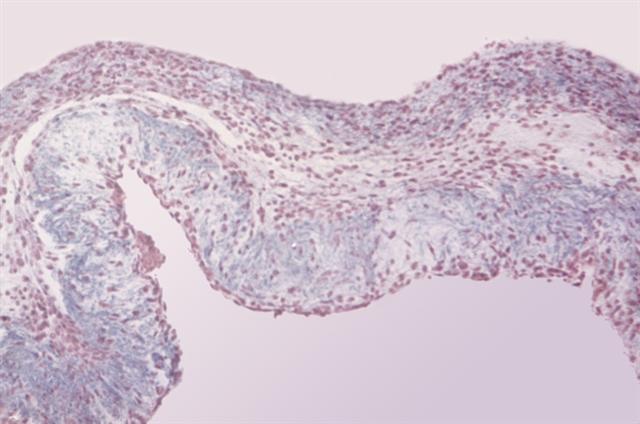

Рис. 2. Микропрепарат створки митрального клапана при эндокардите: отек ткани, инфильтрация полиморфно-ядерными гранулоцитами; окраска по Маллори; ´100.